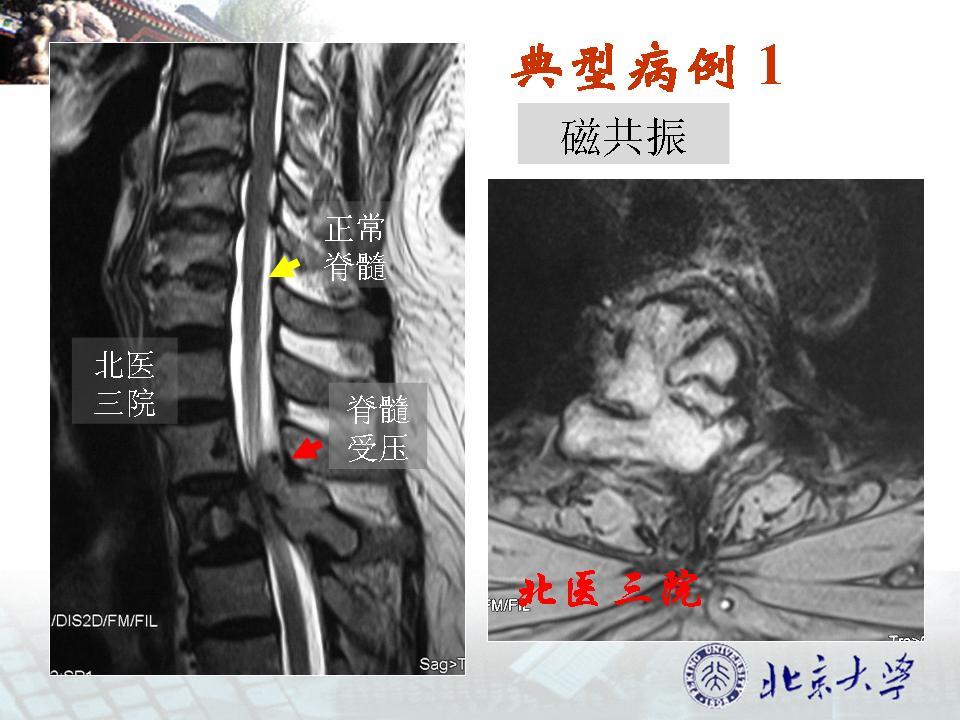

长时间玩手机或致"脑子漏水",这些征兆一定要留意!

国外看医生,拍片说基本上也都是正常的,好像只有t2还是t3有损伤什么的

工作必备!椎间盘的突出,膨出,脱出和髓核游离,你会鉴别吗?